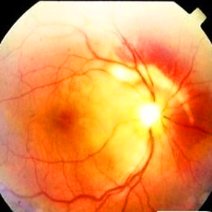

简介:糖尿病视网膜病变,糖尿病性视网膜病变(Diabetic Retinopathy,DR)常被称作糖尿病视网膜病变,指一系列由糖尿病导致视网膜微血管损害引起的病变,是常见的糖尿病慢性并发症之一,也是导致成人失明的主要原因之一。本病严重威胁糖尿病患者生存质量的同时,也给社会带来严重的经济负担。

- 糖尿病视网膜病变糖尿病视网膜病变是什么意思糖尿病性视网膜病变属于糖尿病的严重并发症的一种,是糖尿病性微血管病变中最重要的表现,是一种具有特异性改变的眼底病变,根据是否出现视网膜新生血管为标志,将没有视网膜新生血管形成的糖尿病性视网膜病变称为